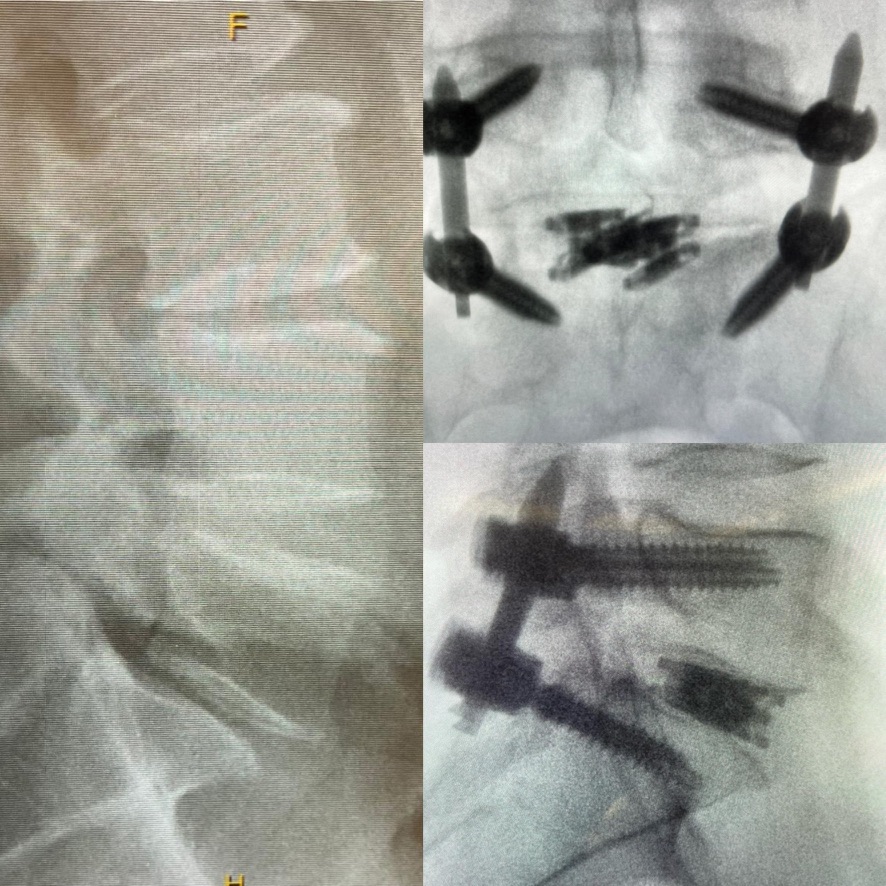

dualX®Slim transforms the fusion environment from insertion to spinal restoration by delivering a powerful dual-expanding implant through a minimally-invasive or endoscopic approaches. dualX®Slim has one of the smallest insertion profiles in the market while still expanding in both horizontal and vertical directions to provide an ALIF-sized final geometry with higher degrees of lordosis (8°, 12°, 15°, 18°*) through the patented trueLordosis™ technology.

Lateral expansion establishes stable footprint Large, center bone graft chamber for post-expansion grafting

20 mm Fully Expanded Width

Powerful vertical expansion restores disc height for decompression

Vertical expansion assists in direct and indirect decompression Multiple lordotic angles restore sagittal balance

8°, 12°, 15°, 18°*

Now, the dualX® and the slim cage have really changed how I treat L4-5. Compared to the laterals, I can put in a cage that nearly matches the lateral size. Also, it nearly matches the ALIF cages when I use a dualX® for the TLIF.

The way it expands, the way it restores the alignment. The way it is locked in. The way it is inserted. Everything from the incision to the insertion to the closure—everything is designed very, very thoughtfully. So I'm very excited about this cage.